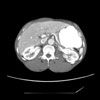

CT scans of the abdomen showed acute infarcts in the medial upper pole and lateral lower pole of the left kidney (Figure). There was no vascular disease in the abdominal aorta, celiac artery, or superior mesenteric arteries. No definite plaque lesions were seen in the right or left renal arteries.

Diagnosis. A CT scan of the abdomen is both sensitive and specific for the diagnosis of renal infarction. With the use of intravenous contrast, renal arteries can also be evaluated for plaques or clots. Sagittal reconstruction through the abdominal aorta can adequately demonstrate findings in the aorta, celiac trunk, and superior mesenteric arteries. Coronal reconstruction of the renal arteries is usually best.